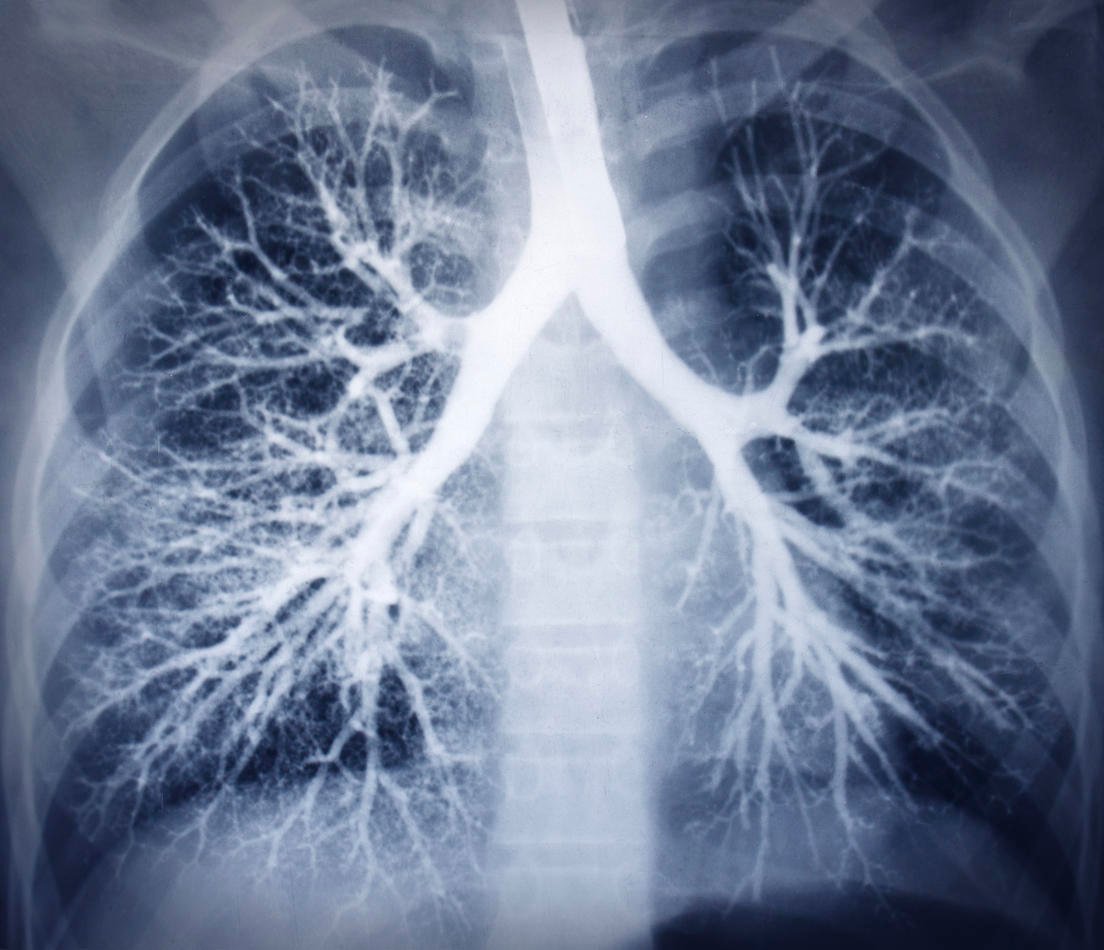

bronchoscopie image radiographie thoracique en bonne santé

Istock

©iStock